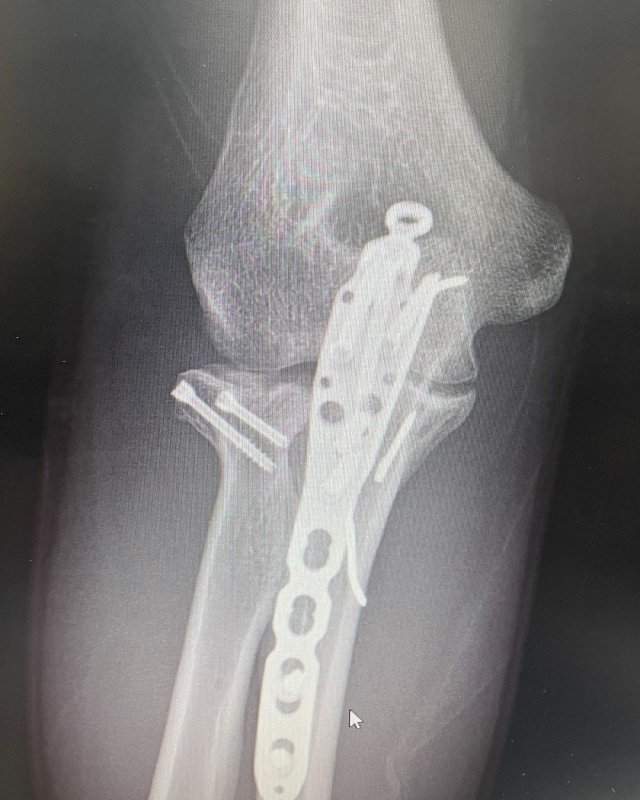

힙합그룹 다이나믹듀오 개코가 팔 골절 수술 후 근황을 밝혔다.

개코는 2일 자신의 사회관계망서비스(SNS)를 통해 “오늘 엑스레이 찍었는데 뼈가 거의 다 붙었다”라며 “그래서 내일 모레 개작실 싱글 발매”라는 글과 함께 여러 장의 사진을 게재했다.

공개된 사진에는 개코가 야외에서 의자에 앉아 있는 모습이 담겼다. 이어 철심이 박힌 엑스레이 사진도 함께 공개했다.

개코는 앞서 지난해 7월 오른팔 골절상으로 수술을 받고 회복에 전념해왔다.